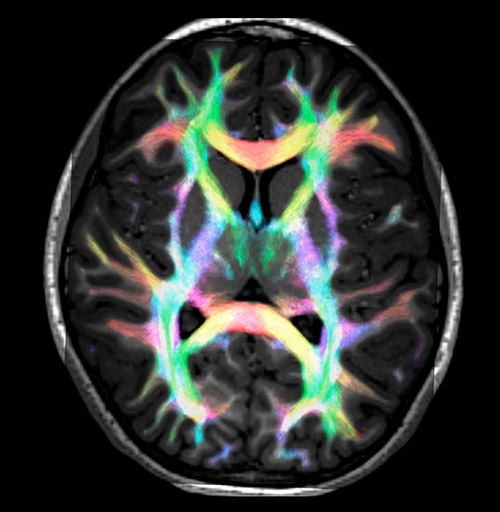

All images were created from the same acquisition in a child using Ingenia 3.0T CX and 32-channel dS Head coil. Diffusion data was acquired at b-values 0, 500, 1000, 2000, 3000. The use of high b-values (3000 s/mm2) effectively suppresses extra-axonal water signal and provides high angular resolution.

DEC TDI

Super-resolution directionally encoded color track-density imaging overlaid on T1-weighted structural MRI.

Super-resolution directionally encoded color track-density imaging